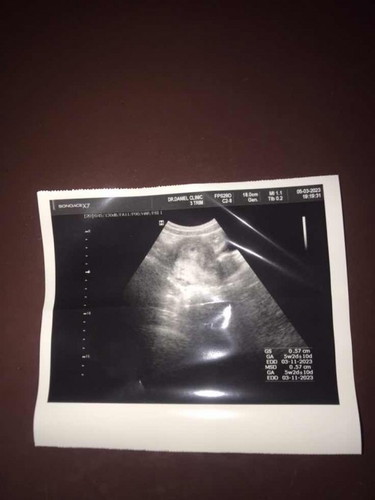

ในนี้บอก6w4d ไปอัตราซาว์ดมาหมอบอก5w อันไหนตรงหรอคะ

ของเรานับประจำเดือนตอนไปซาวคือ 7 W เพราะเราจดวันประจำเดือนทุกเดือน แต่ไปซาวครั้งแรกเจอแต่หัวใจวัดขนาดเท่ากับ 6W หมอยึด6W นับวันคลอด แต่พอไปซาวครั้งที่ 2 ตามนัดคือ 10W เป๊ะ แต่วัดขนาดน้อง เป็น 10W+4 D ใกล้เคียงกับวันที่เราแจ้งประจำเดือน แต่หมอก็ยึดครั้งแรกที่ซาว บอกบวกลบได้ 2W ไม่เป็นอะไรค่ะ